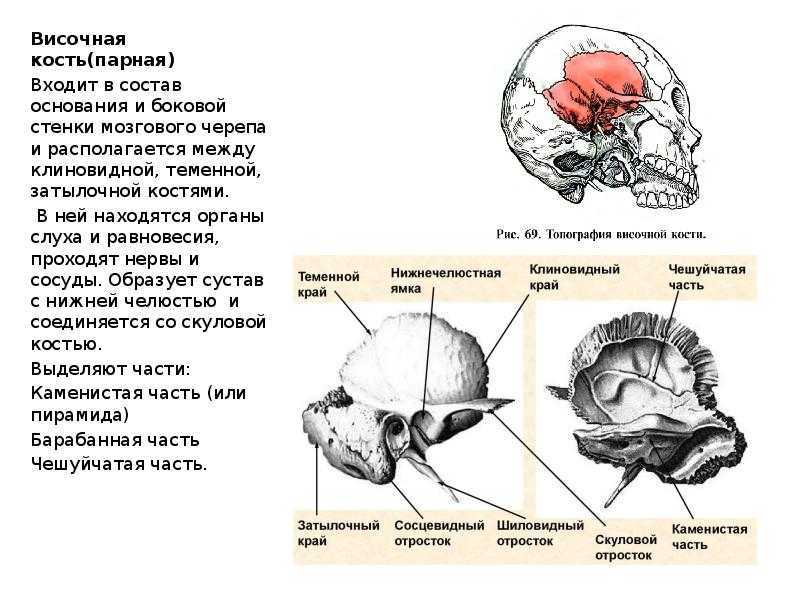

Анатомия сосцевидного отростка